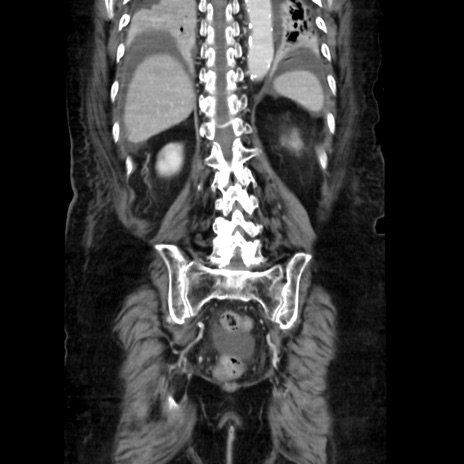

症例40(冠状断像)

【症例】90歳代女性

【主訴】腹痛・嘔吐

【現病歴】 食欲低下、嘔吐があり昨日他院受診。肺炎と診断され入院となる。入院後より腹部全体に圧痛あり。胃管留置され経過みていたが、症状持続するため、

当院転院となる。

【既往歴】胸椎圧迫骨折、胆石症

【身体所見】腹部:中央に激痛あり、圧痛あり、反跳痛不明

【データ】WBC 17100、CRP 18.82

冠状断像